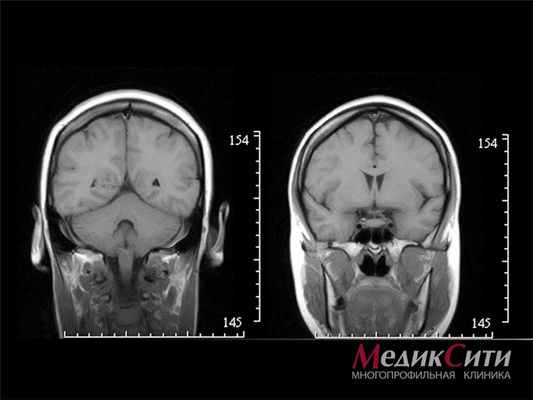

МРТ головного мозга